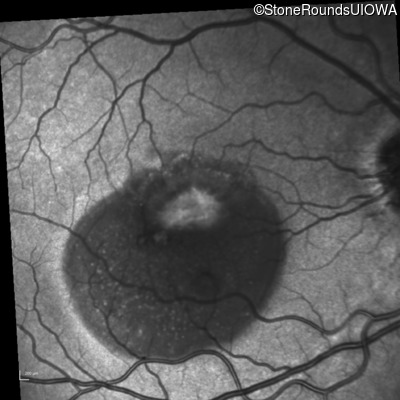

Fluorescein Angiography - Right - 20/40 +1 sc

Exemplar